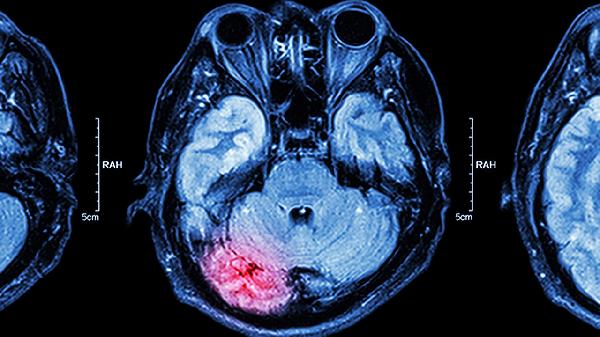

脑肿瘤引起的症状多与占位效应相关,随着肿瘤增大,头痛逐渐加重且持续存在,可能伴随晨起呕吐、视乳头水肿等颅内压增高表现。部分患者出现癫痫、肢体无力或语言障碍,影像学检查如CT或MRI可发现明确病灶。脑神经痛则具有突发突止的特点,疼痛局限于特定神经分布区,如三叉神经痛常累及面部,舌咽神经痛多影响咽喉部,通常无影像学异常,但需排除肿瘤压迫神经的继发性疼痛。

三叉神经痛可能因血管压迫神经根导致,表现为刷牙、咀嚼时诱发的剧烈疼痛,卡马西平片对原发性神经痛有效。舌咽神经痛则与咽喉部触发点相关,吞咽动作易诱发疼痛,加巴喷丁胶囊可能缓解症状。若疼痛伴随进行性神经功能缺损或影像学异常,需考虑听神经瘤、脑膜瘤等肿瘤压迫,此时甲钴胺片可辅助营养神经,但手术切除是根本治疗方式。